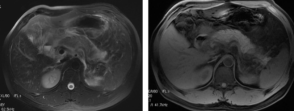

腺炎MRI表现:胰腺局限/弥漫肿大,呈T1低信号、T2高信号;胰腺轮廓清楚或模糊,渗出明显者可有胰周 或胰外积液,呈T1低信号、T2高信号;合并出血,T1T2皆呈高信号;增强扫描:水肿型,胰腺均匀强化 ;坏死型,胰腺不均匀强化,坏死区无明显强化。

截屏2022-10-06 18.55.47